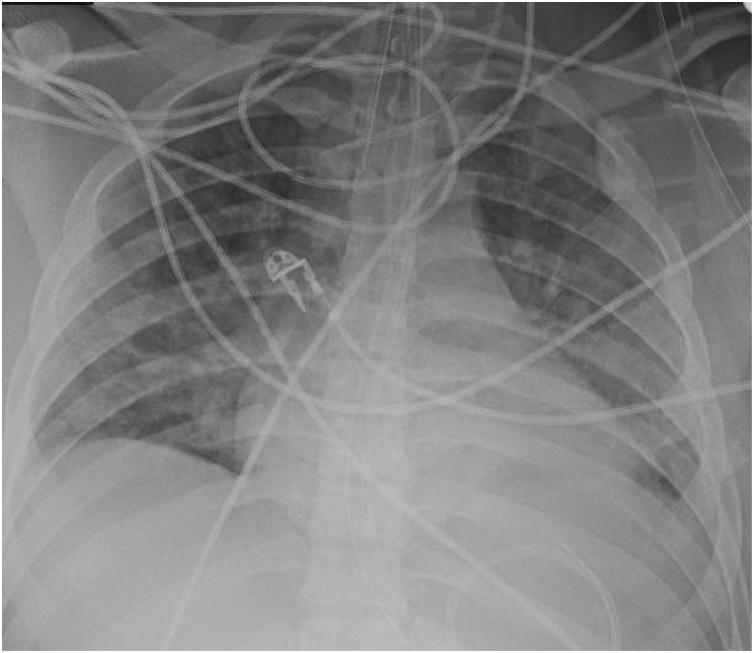

Pulmonary edema is a common clinical entity caused by the extravascular movement of fluid into the pulmonary interstitium and alveoli. The four physiologic categories of edema include hydrostatic pressure edema, permeability edema with and without diffuse alveolar damage (DAD), and mixed edema where there is both an increase in hydrostatic pressure and membrane permeability. As radiographic manifestations and etiologies are varied, an appreciation for both the common and uncommon manifestations and causes of pulmonary edema is essential for accurate diagnosis.

肺水肿是一种常见的临床病症,由液体向肺间质和肺泡的血管外移动所致。水肿的四种生理类型包括静水压性水肿、伴有或不伴有弥漫性肺泡损伤(DAD)的通透性水肿,以及静水压和膜通透性均增加的混合性水肿。由于影像学表现和病因各不相同,了解肺水肿的常见和不常见表现及病因对于准确诊断至关重要。